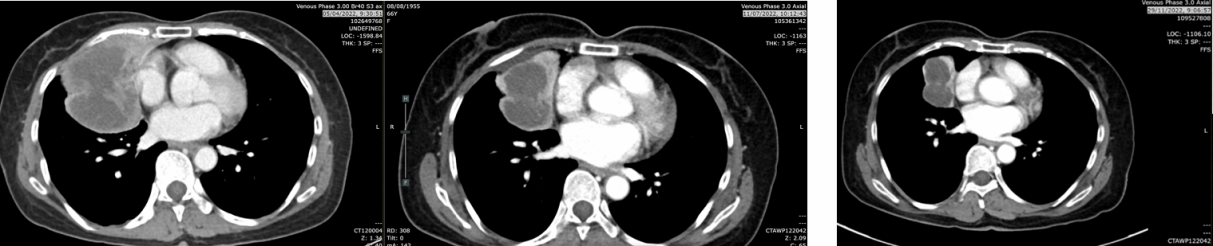

疗效评价:复查CT(2022-07-11),肿块从9.4cm缩小至5.4cm,评估为部分缓解(PR),肺内转移灶及纵隔淋巴结均较前缩小。

复查CT(2022-11-29):肿块5.2cm(缩小),仍维持PR状态,肺内结节缩小至0.5cm,淋巴结部分缓解并出现坏死性改变。

复查CT(2023-02-21):肿块5.3cm,仍维持PR状态。

复查CT(2023-05-19):肿块4.3cm,淋巴结缩小至0.8cm,无肝/肾上腺转移。